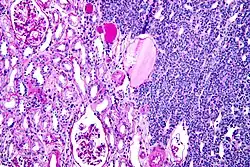

| Micrograph of a metanephric adenoma with structures reminiscent of those seen in papillary renal cell carcinoma. H&E stain. | |

Metanephric adenoma (MA) is a rare, benign tumour of the kidney, that can have a microscopic appearance similar to a nephroblastoma (Wilms tumours),[1] or a papillary renal cell carcinoma.

Metanephric adenoma is diagnosed histologically. The tumours can be located at upper pole, lower pole and mid-hilar region of the kidney; they are well circumscribed but unencapsulated, tan pink, with possible cystic and hemorrhagic foci. They show a uniform architecture of closely packed acinar or tubular structures of mature and bland appearance with scanty interposed stroma.[3][4][5][6][7] Cells are small with dark staining nuclei and inconspicuous nucleoli. Blastema is absent whereas calcospherites may be present. Glomeruloid figures are a striking finding, reminiscent of early fetal metenephric tissue. The lumen of the acini may contain otherwise epithelial infoldings or fibrillary material but it is quite often empty. Mitoses are conspicuously absent.[3][4][5][6][7] In the series reported by Jones et al. tumour cells were reactive for Leu7 in 3 cases of 5, to vimentine in 4 of 6, to cytocheratin in 2 of 6, to epithelial membrane antigen in 1 of 6 cases and muscle specific antigen in 1 of 6.[5] Olgac et al. found that intense and diffuse immunoreactivity for alpha-methylacyl-CoA racemase (AMACR) is useful in differentiating renal cell carcinoma from MA but a panel including AMACR, CK7 and CD57 is better in this differential diagnosis.[8] Differential diagnosis may be quite difficult indeed as exemplified by the three malignancies initially diagnosed as MA that later metastasized, in the report by Pins et al.[9]